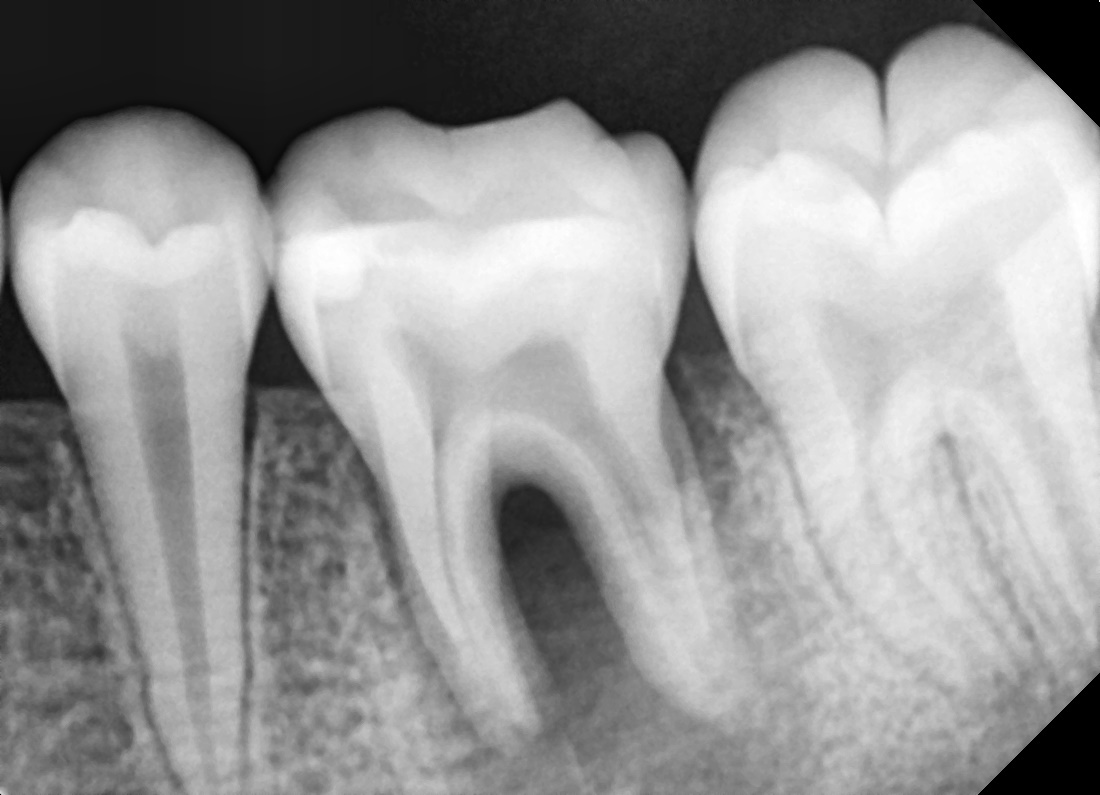

재신경치료

다른 병원 치료 후 재발한 어금니

Before

After

재신경치료로 추가 근관을 찾아 1년 9개월 후 완치